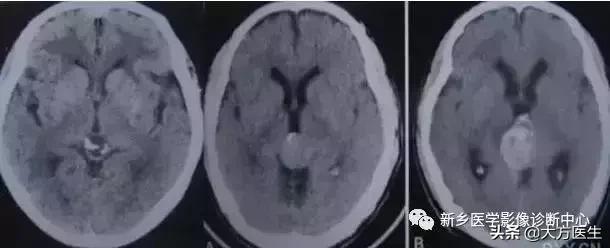

17、转移瘤

转多瘤钙化罕见,主要为骨肉瘤和乳癌转移,也可见于肺癌转移。

左2为肺癌转移,右1为乳癌转移